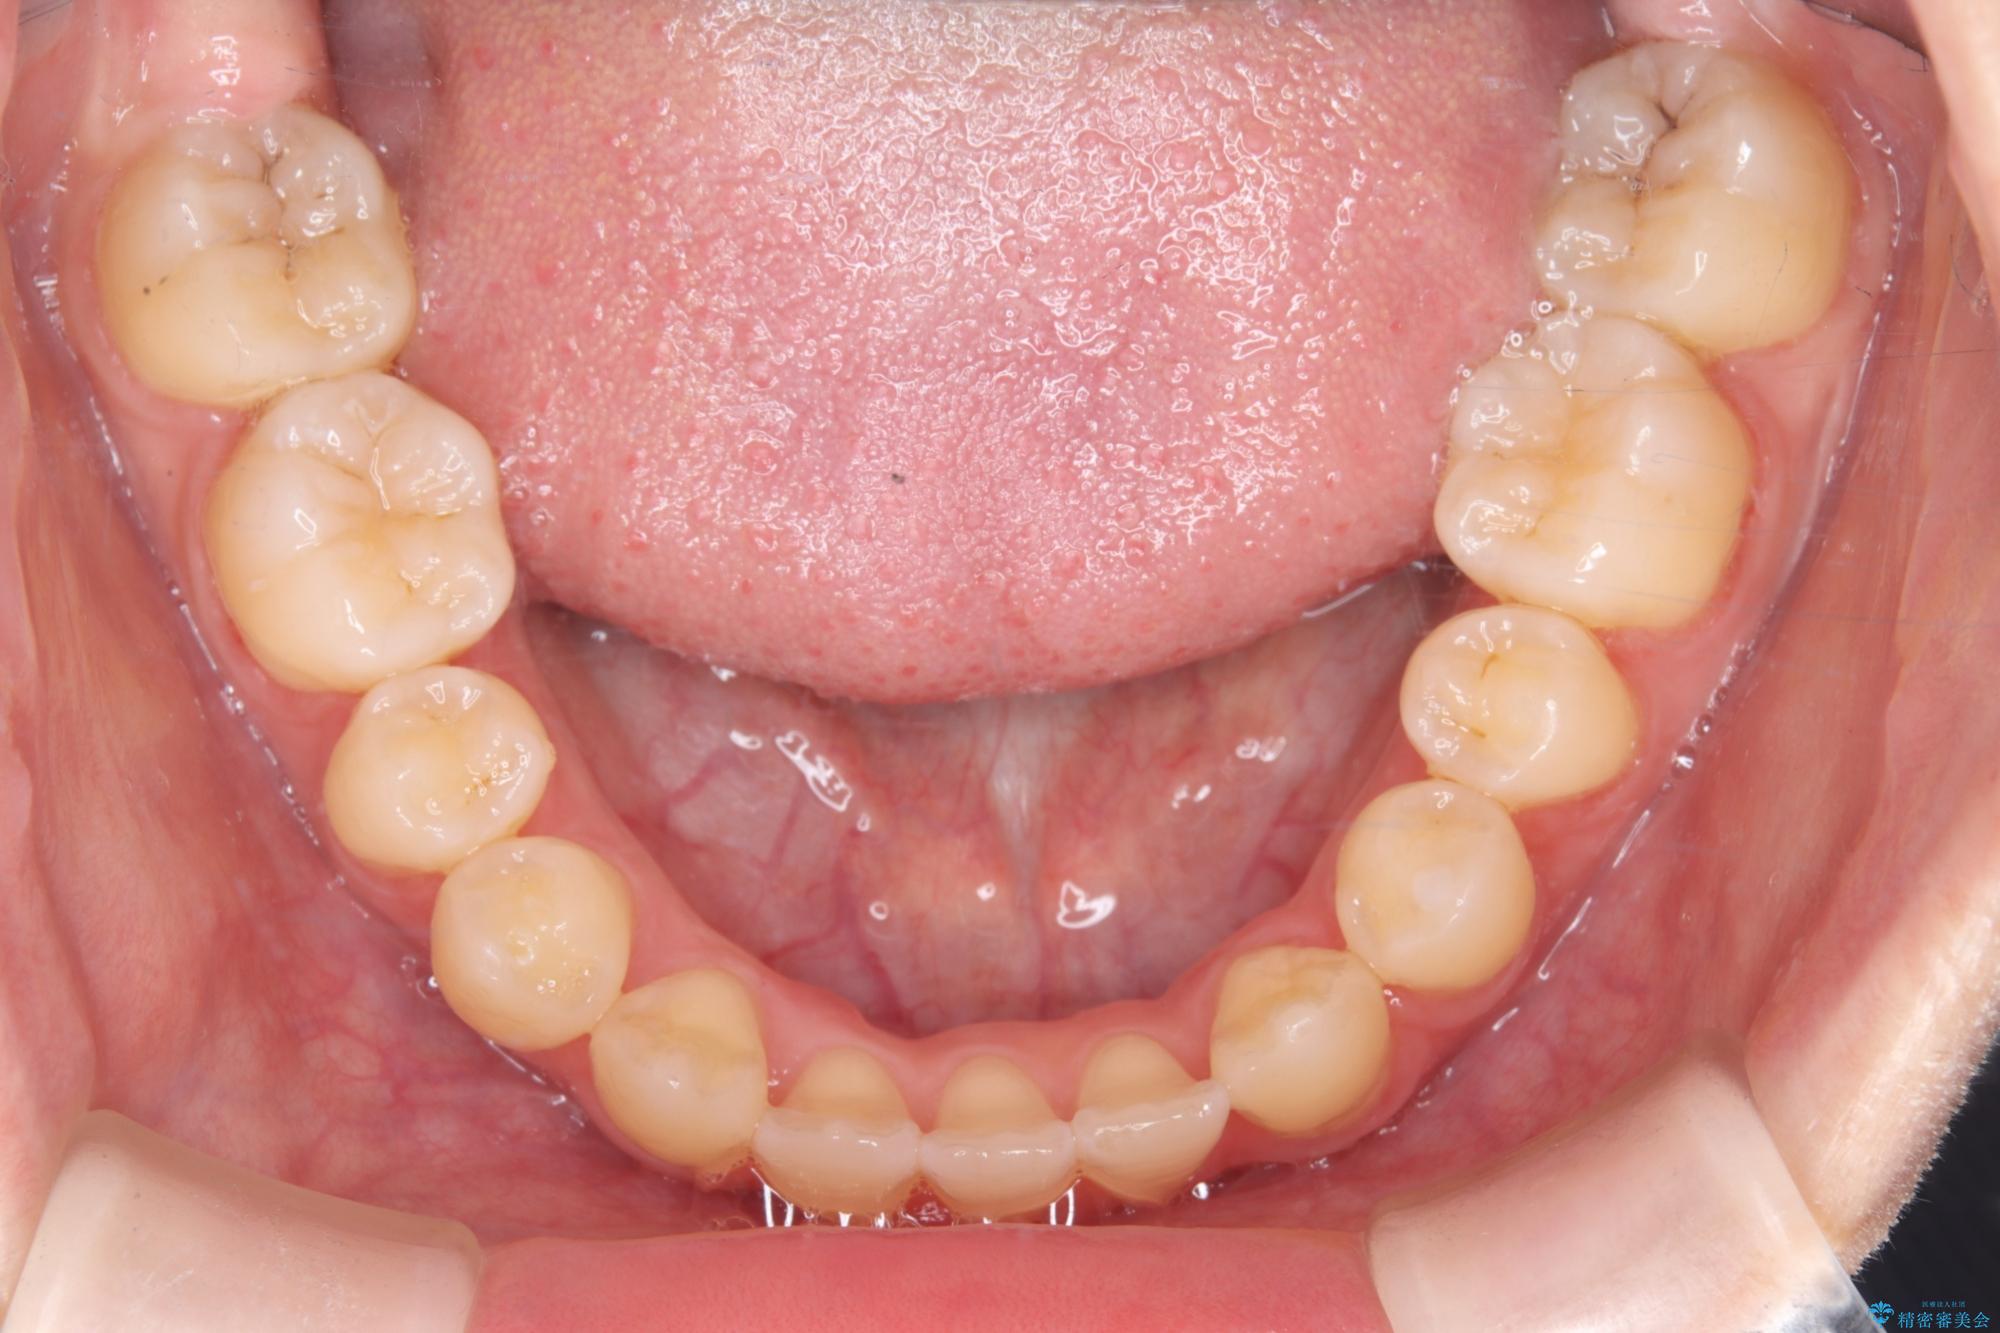

診査の結果、すでに下顎前歯の抜歯が行われていましたが、マウスピースの適合が著しく悪くなっており、歯が計画通りに動いていない状態でした。また、歯を支える骨の厚みや歯肉の薄さを考慮すると、このままマウスピースによる傾斜移動を続けるのは歯肉退縮(歯茎が下がること)のリスクが非常に高いと判断。

安全かつ確実に抜歯スペースを閉じ、咬み合わせを完成させるため、マウスピースから**ワイヤー矯正(マルチブラケット装置)**へ切り替えるリカバリープランを提案しました。

装置の変更と歯肉への配慮: ワイヤー矯正は歯の根(歯根)を平行に移動させる「歯体移動」を得意としています。本症例では、歯肉退縮を防ぐために、歯の傾きを精密にコントロールしながら抜歯スペースを閉じる必要がありました。ワイヤー装置を用いることで、インビザラインでは難しくなっていた三次元的な細かい調整を可能にしました。